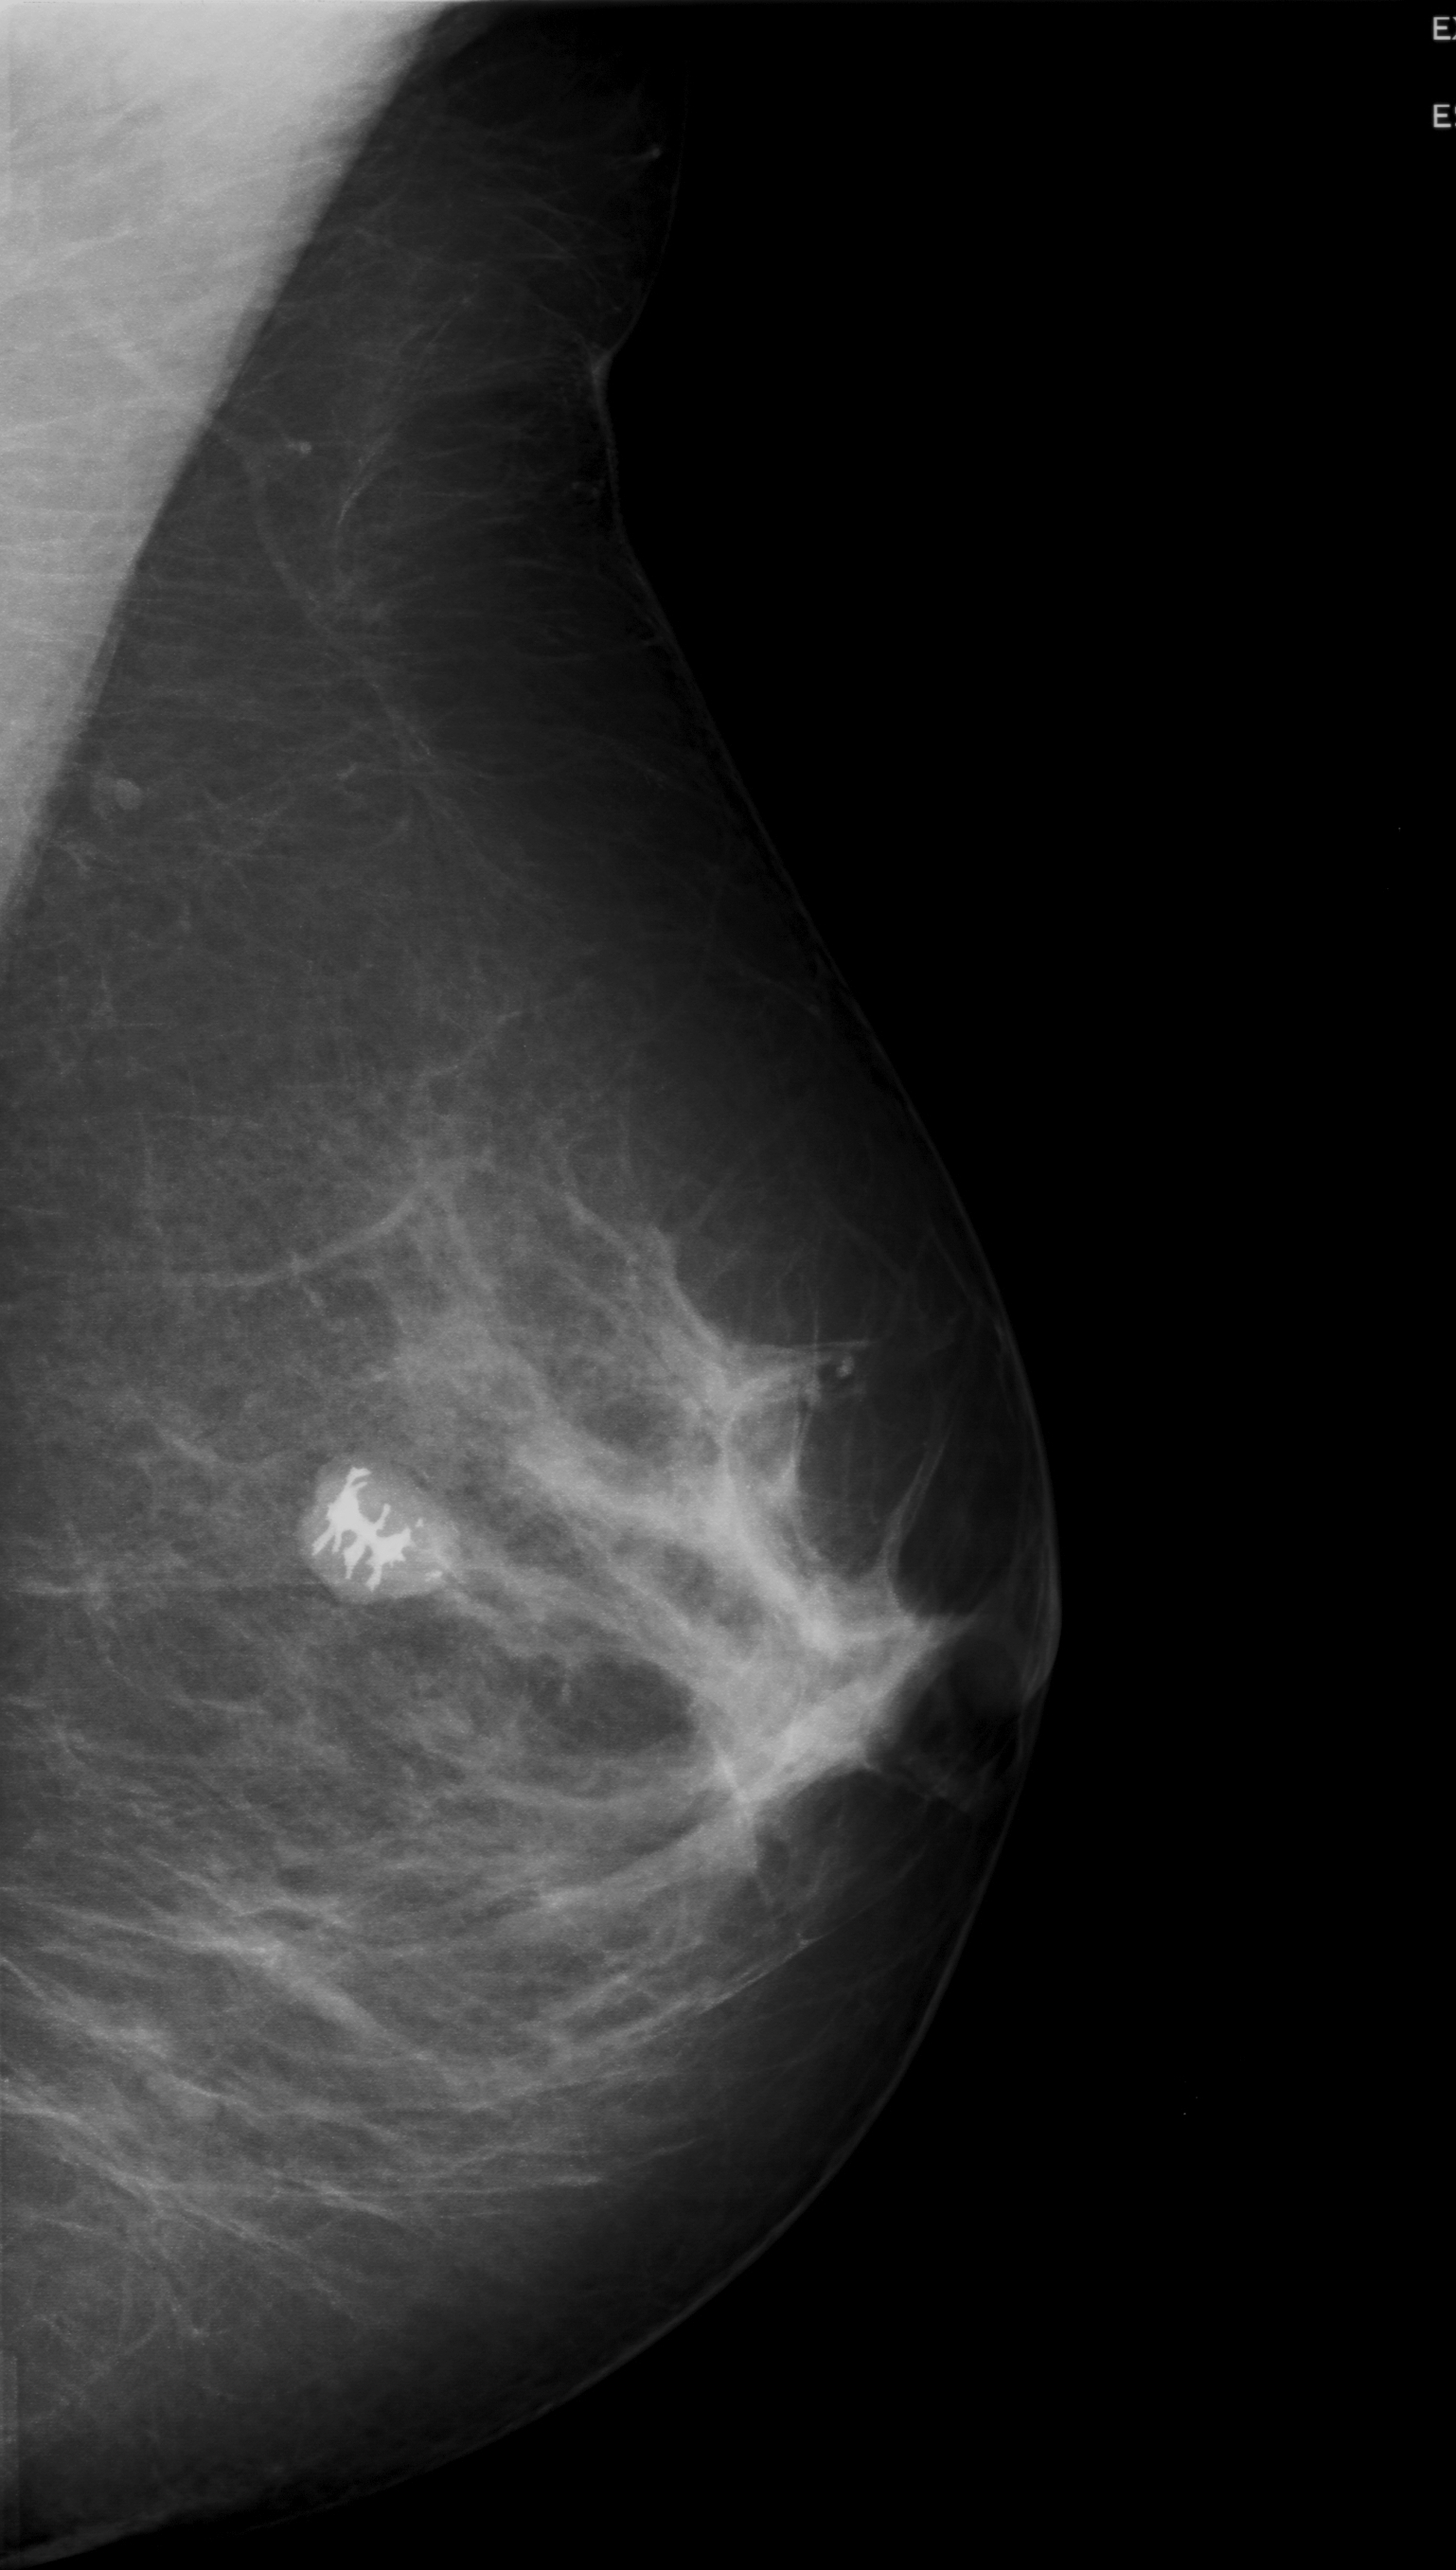

Фиброаденома молочной железы - доброкачественное образование, которое часто встречается у женщин. Оно может быть обнаружено при помощи различных методов диагностики, включая маммографию. Ниже представлены фотографии, помогающие понять, как выглядит данное заболевание.

Маммограмма кальцинаты визуализируются

Кальцинаты маммограмма

Маммография и ее роль в диагностике фиброаденомы молочной железы

Маммография - это рентгенологическое исследование молочных желез. Оно позволяет выявить различные изменения в тканях, включая фиброаденому. На маммограммах можно увидеть структурные особенности опухоли и отследить ее динамику во времени.